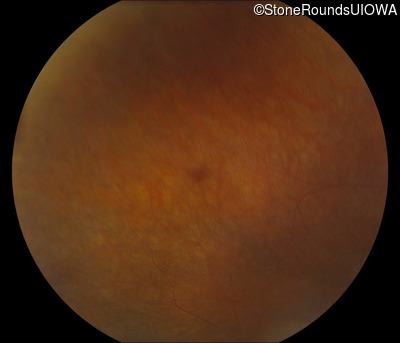

Fundus Photography - Right - 5/180

Exemplar